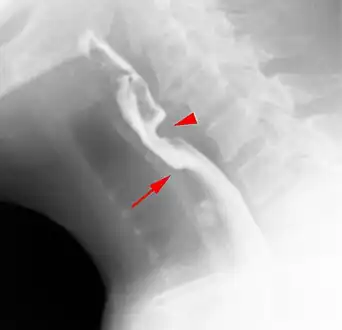

The diagnostic test of choice is a barium swallow.

Esophageal webs are thin 2–3 mm (0.08–0.12 in) membranes of normal esophageal tissue consisting of mucosa and submucosa that can partially protrude/obstruct the esophagus. They can be congenital or acquired. Congenital webs commonly appear in the middle and inferior third of the esophagus, and they are more likely to be circumferential with a central or eccentric orifice. Acquired webs are much more common than congenital webs and typically appear in the cervical area (postcricoid).